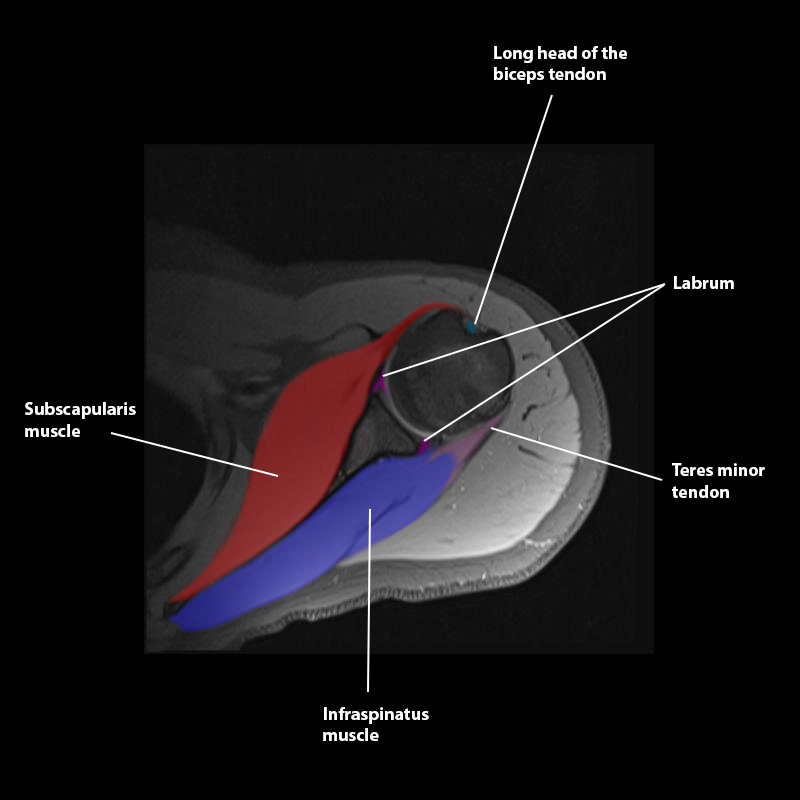

Shoulder MRI Anatomy